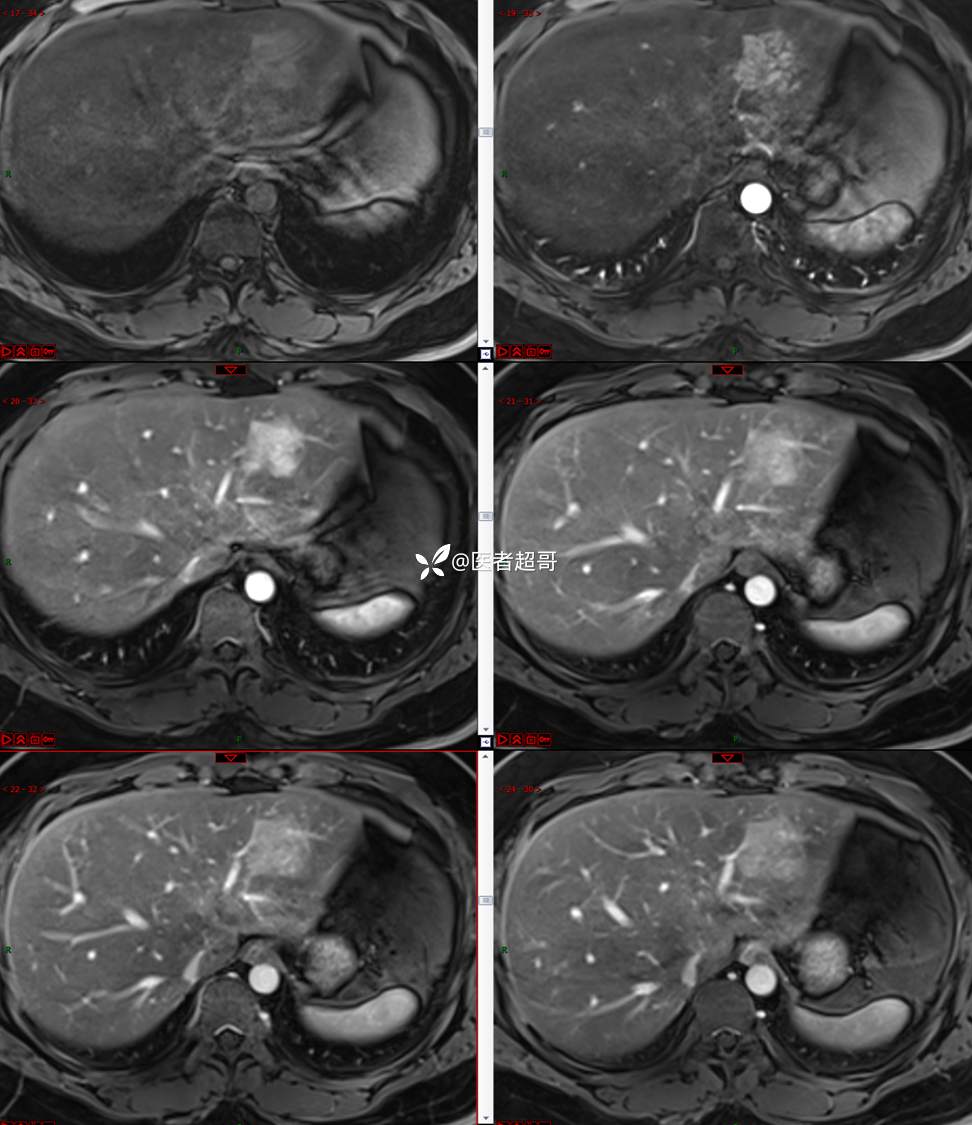

【影诊笔记800】青年男性,肝脏占位,特殊对比剂提示富血供,您能想到啥?有结果!

现病史:患者缘于5天前体检时发现肝占位性病变,未予以特殊处置。现患者为求系统诊治就诊于我院,行普美显提示:肝左叶富血供占位,请结合临床及其他检查,肝多发血管瘤,脂肪肝,肝囊肿,请结合临床。门诊以“肝占位性病变”收入我科。病程中,饮食睡眠可,二便可,近期体重未见明显变化。